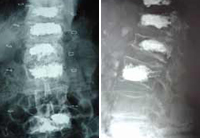

![]() Kyphoplasty of L2 |